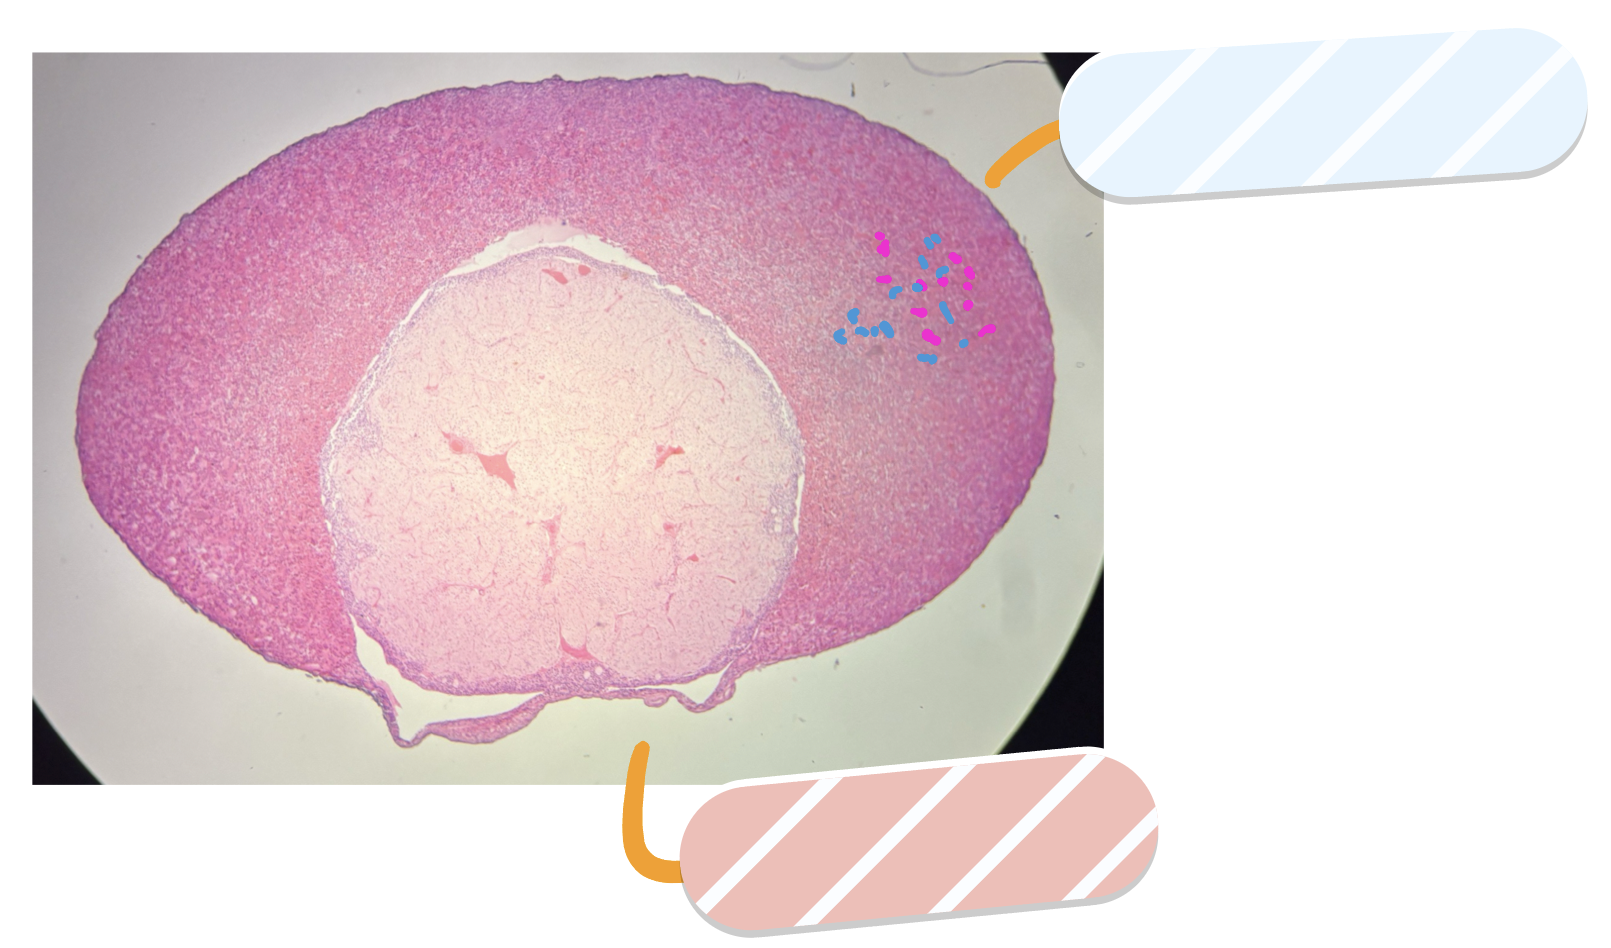

What is this a slide of?

Ovary

What is red?

Cortex

What is orange?

Corpus luteum

What is yellow?

Mature tertiary follicle

What is green?

Antrum